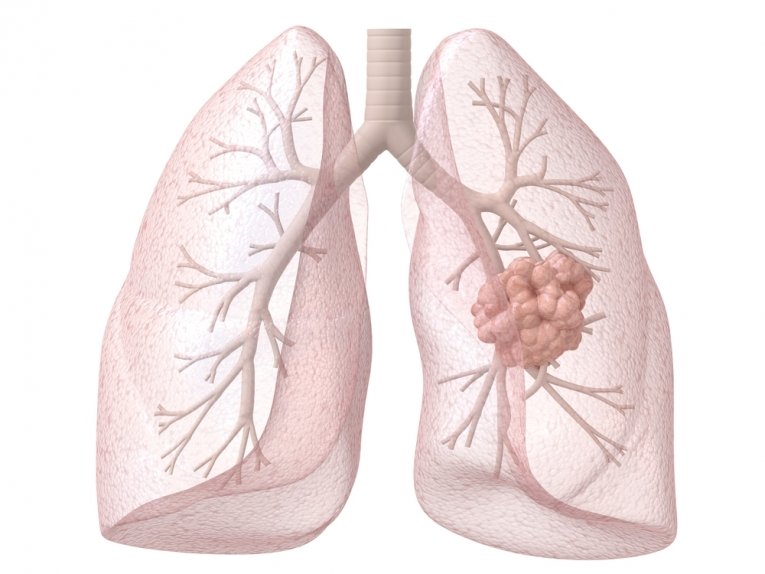

Формирование злокачественного новообразования легких происходит достаточно медленно. Диагностика порою бывает затруднительна, поскольку многие симптомы неспецифичны и принимаются специалистами за проявления иных легочных патологий. Нередко до обращения в специализированную клинику ситуация доходит до крайности – у пациента диагностируют уже рак легких 4 степени, что существенно затрудняет лечение и ухудшает прогноз выживаемости.

Рак легких 4 стадии имеет и специфические проявления – дыхательные расстройства. На 2-3 этапе формирования патологии они не столь показательны, но к моменту выхода метастазов в иных органы, степень их интенсивности такова, что постановка адекватного диагноза не вызывает у специалистов затруднений.

- Прогрессирующая одышка – захват опухолевым процессом все большего количества паренхимы органа провоцирует затруднение с дыхательной деятельностью у пациентов. Часто комбинируется с расстройством в сердечнососудистой системе – приступы стенокардии напряжения, что еще более усугубляет положение, продолжительность жизни сокращается.

- Кровохарканье – выделяемая при кашле мокрота может быть окрашена лишь в едва заметный розовый цвет в начале появления заболевания, в дальнейшем, когда наблюдается финальный этап патологии, она напоминает «ягодное желе». При прорастании опухоли в крупный сосуд у пациента остро возникает массивное легочное кровотечение, вплоть до летального исхода.